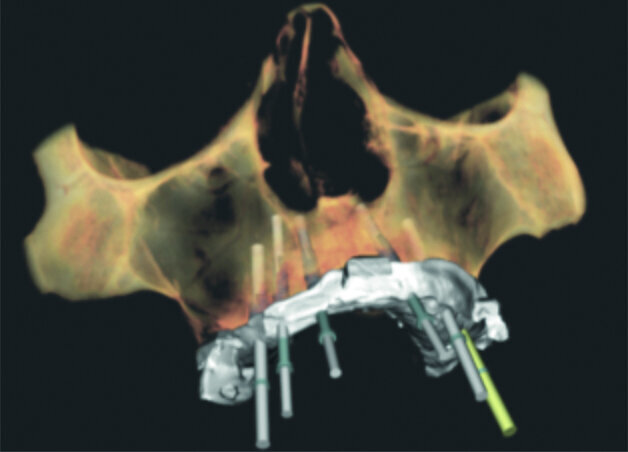

Fig. 9 : Empreintes optiques matchées avec le CBCT et la planification implantaire.

Un grand changement dans nos protocoles se met en place avec l’arrivée des empreintes réalisées à l’aide d’une caméra optique. En effet celles-ci nous permettent de « matcher » les informations cliniques précises en complément de l’imagerie osseuse avec une transmission immédiate, sans déformation d’informations vers le prothésiste (Fig. 9). Nous pouvons ainsi programmer une mise en charge immédiate ultra précise, à l’aide d’un bridge fabriqué en amont de la chirurgie et vissé le jour de celle-ci !